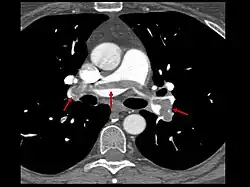

- Le scanner spiralé des artères pulmonaires[13] ou angioscanner des artères pulmonaires : un produit de contraste iodé est injecté en intraveineux. Le mouvement rotatif et longitudinal (caractère spiralé) de la tête du scanner permet de bien visualiser les artères pulmonaires proximales et moyennes et un peu moins bien leur distalité. C’est un excellent examen de diagnostic positif et de gravité, même si les risques liés à l’emploi de produits iodés et la radiation persistent. Il est moins invasif que l'angiographie conventionnelle. Il permet aussi l'évaluation de plusieurs autres structures intrathoraciques (aorte et médiastin, poumon, plèvre), en plus de l'évaluation des artères pulmonaires. Il est considéré souvent comme le nouvel examen de référence.